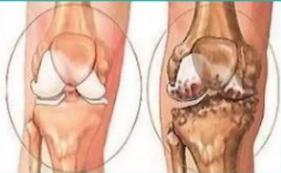

膝关节的骨关节炎最初的病理改变发生在关节软骨,主要表现为软骨的磨损,变薄。正常的关节软骨就像生活中常见的垫片一样,覆盖在膝关节上下骨面上,在关节面之间起缓冲、润滑、维持平衡等作用。

2、如果初期没有得到足够的重视和规范的治疗,骨关节炎继续发展,磨损的关节软骨会越来越薄,最后出现软骨下覆盖的骨质外露,形成上下关节面骨与骨的接触。

这时患者会感觉膝关节非常疼痛,因为骨质表面的神经末梢非常丰富,失去软骨的保护后,神经末梢在运动中受到的刺激增加,便会引起剧烈的疼痛。